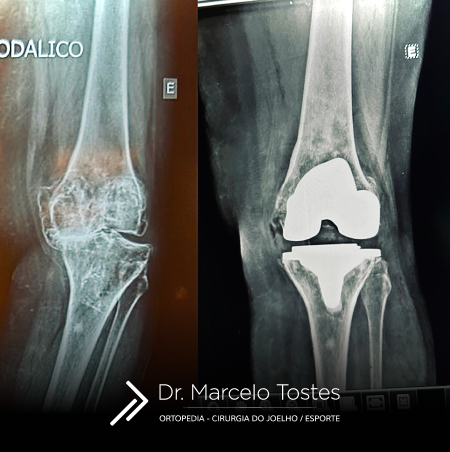

A prótese do joelho nada mais é que um recapeamento da articulação do joelho por implantes metálicos e sintéticos que envolvem os ossos desprotegidos de sua estrutura de proteção nativa (cartilagem). Serve, portanto, para aliviar as dores causadas pela artrose (doença do joelho que elimina / degenera a cartilagem) em condições avançadas. Um joelho que tem artrose avançada dói muito quando usado já que os nossos ossos são vivos e têm nervos que levam o joelho a doer quando perdem sua proteção natural de menisco e cartilagem

Se você imagina o joelho como uma dobradiça tenha certeza de que, na verdade, é muito mais complexo. Para todos os componentes metálicos e sintéticos que constituem a prótese do joelho deve haver uma congruência e similaridade com as superfícies naturais/anatômicas de um joelho normal. Com base na idade, estilo de vida e condições do joelho do paciente, existem diversas opções de design de prótese que podemos escolher para que o paciente possa retomar à sua vida ativa sem complicações. Em última análise, o cirurgião fará uma recomendação do implante (design e marca) com base em sua habilidade e experiência com um dispositivo em particular, bem como suas circunstâncias e necessidades específicas.

O Dr. Marcelo Tostes entende que é extremamente importante que o cirurgião explique as diferenças das próteses ao paciente para que ambos possam tomar as melhores decisões conjuntamente.